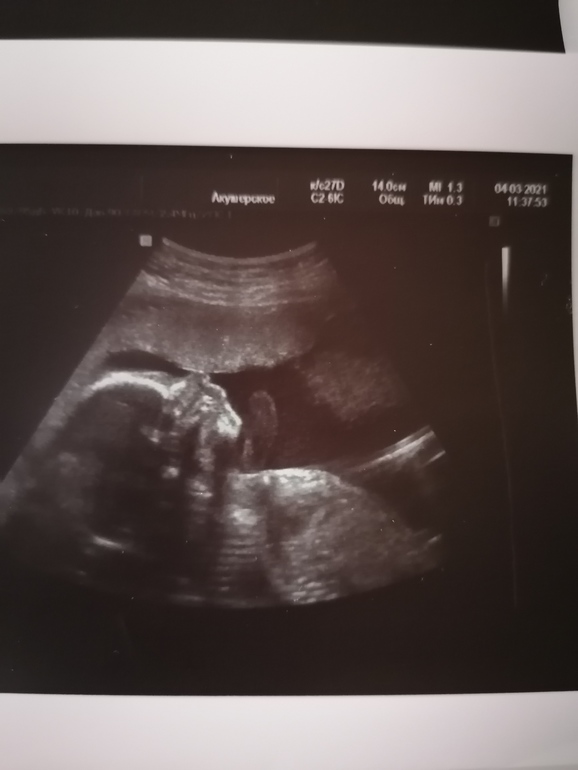

Сегодня ездила на узи в ЦПСИР, ещё раз напомню веду там беременность из-за резус-конфликта. Так вот, сегодня по узи печень в норме, кровоток в зоне С и это значит сынок не страдает тттттт. И дай бог родится отрицательный. Все остальные показатели чётко соответствуют сроку, он перестал сильно опережать. Вес сегодня 532 грамма.

Ну и мой любимый сынок👶🙏🙏🙏🥰